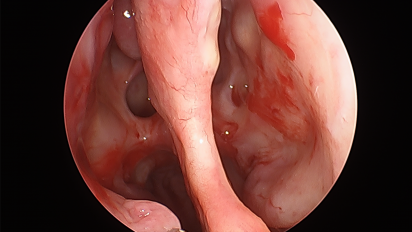

Nasal exam: All patients with suspicion of SANDO should receive a nasal exam to rule out inflammatory, structural, or neoplastic abnormalities in the nasal passage. This is done with a nasal speculum or endoscope, if available.

Dacryocystorhinostomy (DCR) surgically bypasses the nasolacrimal duct and thus is the primary surgery for NLDO. It requires a patent punctum and canaliculus. A fistula is created from the lacrimal sac to the lateral nasal mucosa and a silicone tube is temporarily placed through this fistula to maintain patency. See the EyeWiki article a “Dacryocystorhinostomy” for more details about DCR.

DCR can be approached endoscopically (endonasal, or “endoDCR”) or via an external incision. External DCR is currently the gold standard of lacrimal bypass surgery, and multiple studies show a success rate over 95% for NLDO. Historically, external DCR has had greater success rates to endoscopic DCR. However, more recent studies suggest the success rate of endoDCR is approaching that of external DCR.[1] There is a high learning curve for endoscopic DCR, and this certainly influenced prior studies. Advantages of endoscopic DCR are that it is less invasive, has a shorter operative time, preserves lacrimal pump function, has faster recover, and avoids an external scar. However, the initial cost of endoscopic DCR can be high, including equipment price and the time spent learning the procedure. Endoscopic DCR assisted with laser ostium creation has been shown to have a lower success rate than endoDCR (71% and 83%, respectively in a study comparing the two), but has less bleeding and a quicker recovery time. Some authors suggest endoscopic DCR for the treatment of SANDO, as intranasal abnormalities can be directly visualized during surgery and additional nasal surgery can be accomplished if needed, generally with the assistance of an experienced rhinologist.